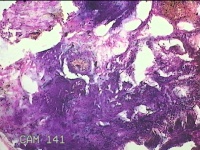

3、7、11点肿物

性别

男

年龄

34岁

临床诊断

1.混合痔 2.肛裂

一般病史

大便出血半年,伴粘液便。

标本名称

大体所见

灰白暗红色肿物1.8x1x0.3cm两个,表面糜烂。

图1

痔是有的。